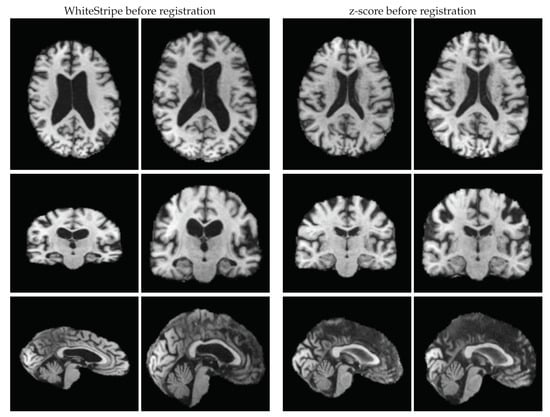

2.2. Equipping FSL-SIENA with Intensity Standardisation

2.3.4. WhiteStripe